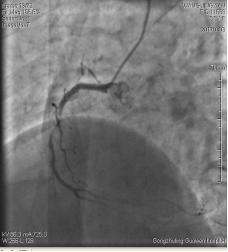

中日聯(lián)誼閆明洲教授向家屬交代病情及介入相關(guān)并發(fā)癥后,患者及家屬同意冠脈支架治療,過程順利,于右冠脈中段植入Firebird2 2.5*33mm 藥物洗脫支架1枚。

術(shù)前 術(shù)后